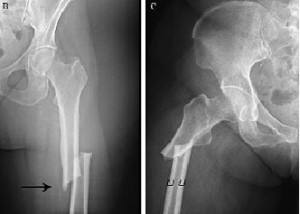

Riesgo de una nueva fractura en mujeres postmenopaúsicas según la intensidad del traumatismo inicial

15 junio 2021

La recurrencia de fracturas se asoció tanto con una fractura inicial traumática como con una de bajo impacto o no traumática. Estos hallazgos sugieren que la evaluación clínica de la osteoporosis debe realizarse luego de ambos tipos de fractura. JAMA Internal Medicine, 7 de junio de 2021.